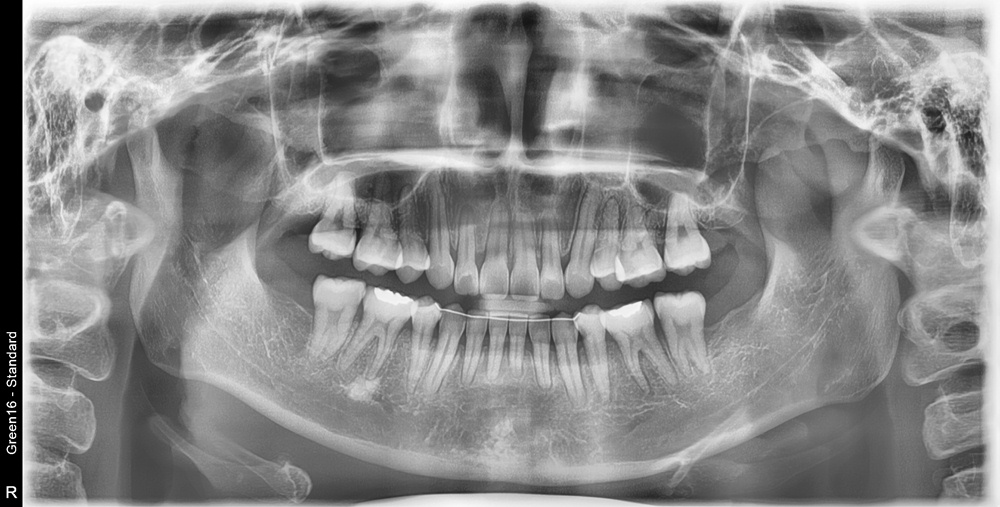

치료 후 사진입니다.